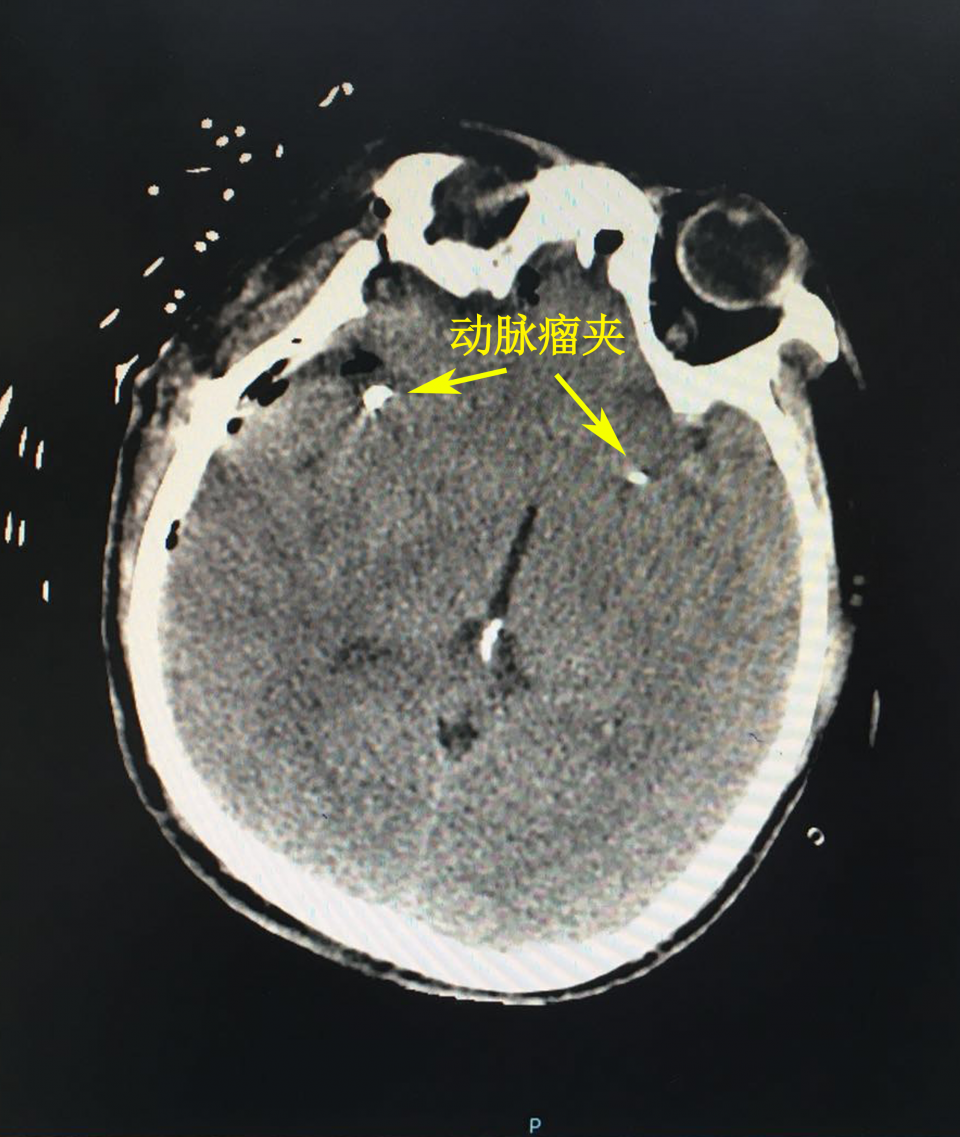

该手术由病区主任王晓健指导,胡阳春副主任医师主刀完成,手术选择从右侧翼点入路,首先暴露右侧大脑中动脉分叉处动脉瘤,术中证实该动脉瘤瘤腔内血栓形成,周边粘连紧密,取动脉瘤夹FT726T将瘤颈塑性夹闭,保留M1-M2主干通畅,并切除瘤体,解除占位,分离出对侧大脑中动脉M1段分叉处动脉瘤,再用另一枚FT726T型动脉瘤夹夹闭瘤颈,穿刺证实动脉瘤夹闭完全,大脑中动脉主干保留完好。术后患者恢复良好,肢体活动正常,嗅觉不受影响,未遗留任何功能障碍。